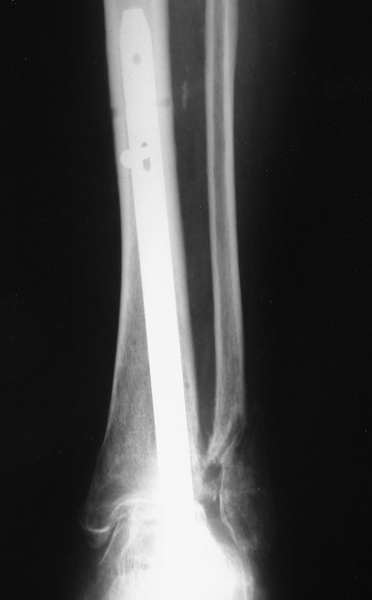

Можно: 65-летняя пациентка, оперирована по поводу несросшегося в гипсе перелома лодыжек с патологической вальгусной установкой стопы и выраженным нарушением опрной функции. Оперирована через 6 месяцев после травмы. Рентгенограммы через 4 месяца после операции.